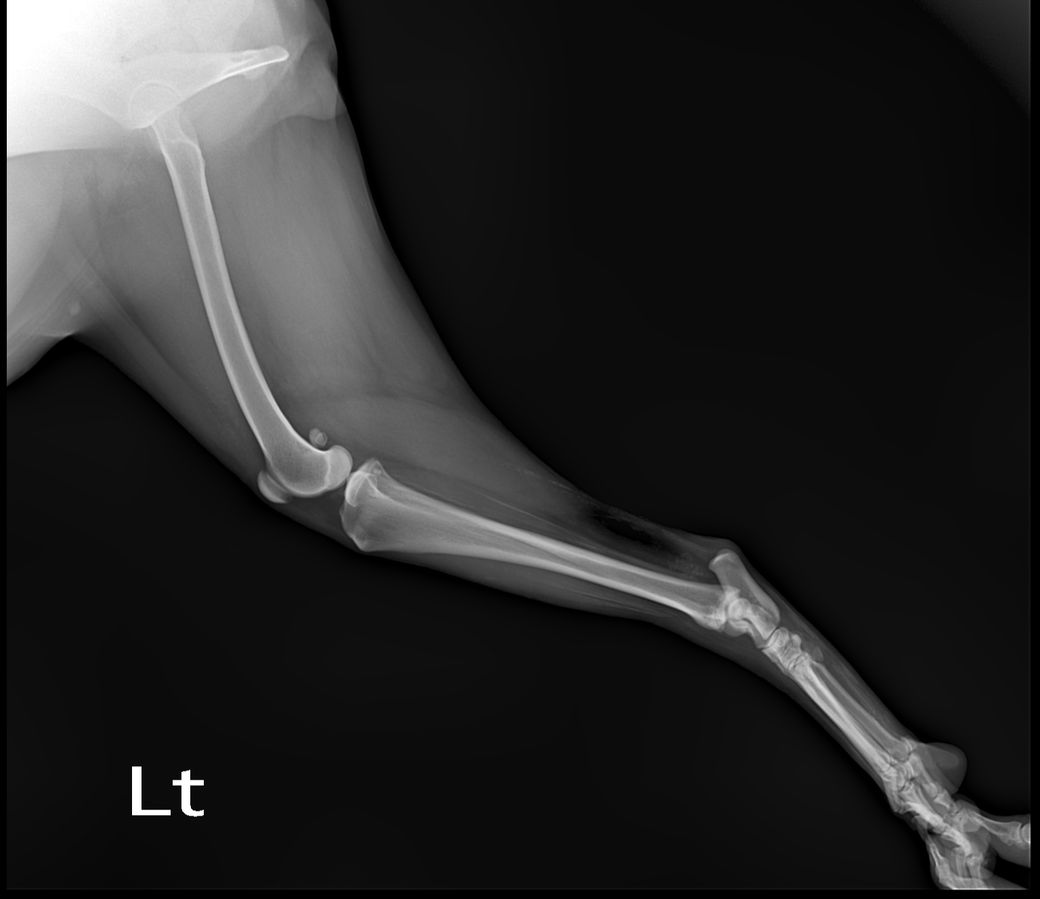

정상 발 사진

화살표로 표시된 부분의 근육 혹은 인대의 석회화 양상이 매우 뚜렷한 양상을 보이고 있고, 이는 양측 후지 모두에서 관찰되는 바 대사성 질환이나 전신성 질환이 있을 가능성이 높고,

화살표 한 부분이 반대쪽에 비해 부종 양상이 명확하게 관찰되기 때문에 근육 및 인대의 석회화를 유발하는 질환 https://diamed.tistory.com/1023 이 원발로 있다가 충격에 의해 인대나 근육이 찢어졌을 가능성이 높다는것을 의미합니다.